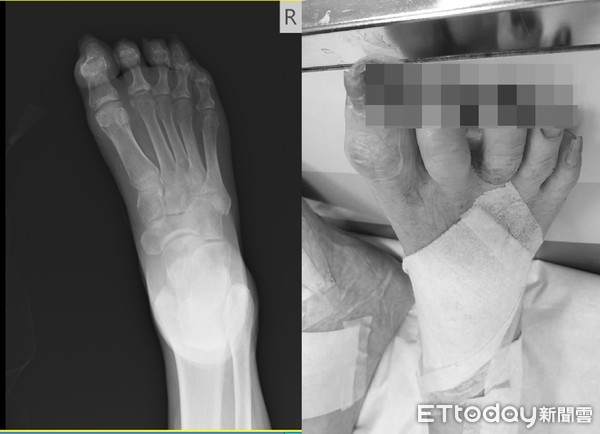

▲老伯用水果剪刀自行修剪指甲,沒想到竟意外剪斷腳趾。(圖/豐原醫院提供,下同)

陳明澤表示指出,該名老伯因難耐腳趾甲變長,拿了較大、較鋒利的水果剪刀修趾甲,不料將腳趾頭給剪掉,還剪掉骨頭一小部分,造成開放性傷口,到院後因為傷口無法完全縫合,因此將傷口覆蓋保護,讓它自然癒合。

▲豐原醫院外科醫師陳明澤指腳趾甲誤剪位置,經治療已經長出肉。